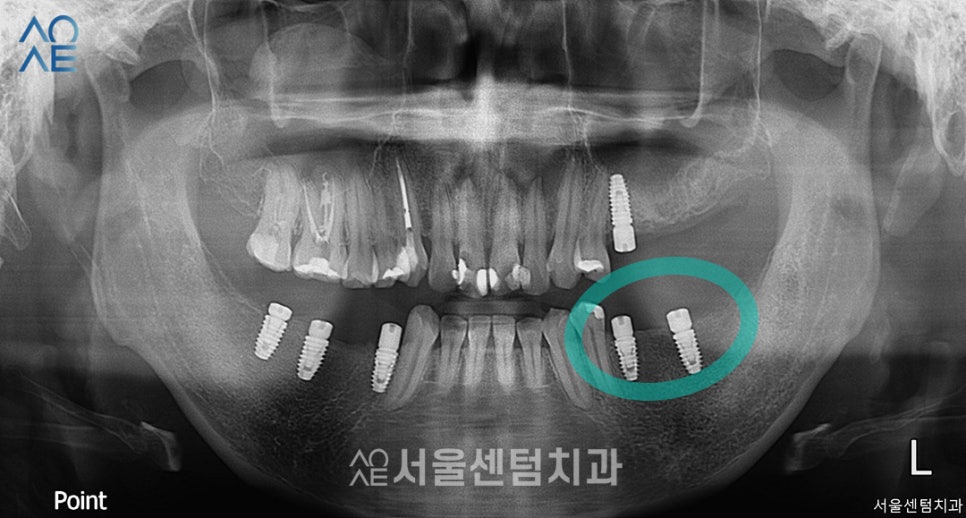

1년 넘게 내원하시면서

임플란트와 신경치료를 마무리했고

이 엑스레이는 정기검진때 촬영했습니다.

성공적인 30대임플란트 결과

이렇게 전/후 사진을

나란히 놓고 보니 차이가 확연하네요.